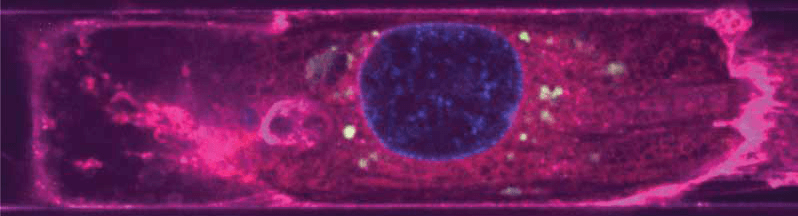

Endothelial-derived EVs (green) around the nuclei (blue) of a cardiomyocyte (magenta). (Image courtesy of the Disease Biophysics Group/Harvard SEAS)

The researchers found that in tissues treated with EEVs, the cardiomyocytes could better adapt to stress conditions and sustain a higher workload.  The researchers induced injury by three hours of oxygen restrictions followed by 90 minutes of reoxygenation and then measured the fraction of dead cells and the contractile force of the tissue. The heart tissue treated with EEVs had half as many dead cells and had a contractile force four times higher than the untreated tissue after injury.